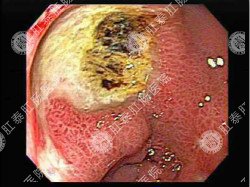

想知道慢性胃炎的症状,首先要知道它的分类。慢性胃炎,按病理发展可分为浅表性胃炎和萎缩性胃炎。

这是慢性胃炎的早期阶段,病变仅局限于胃小凹和粘膜固有层的表层。其临床表现为慢性不规则的上腹疼痛、嗳气、腹胀等,部分患者可能出现反酸、上消化道出血等症状。

2、萎缩性胃炎。

是慢性胃炎的进展性阶段,通常可蔓延到不同部位,发展成不同类型。其临床表现为出现明显厌食症状、体重减轻、舌头发炎、舌乳头萎缩等,部分患者可能会伴随有贫血症状。